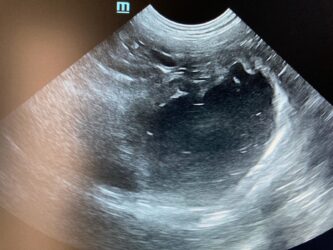

Dimitri, CV, 9.6kg, 11j, MC, bijgeruis 4/6 waarvoor hij vetmedin krijgt en opgevolgd wordt door cardioloog:

21/08/2025: Bij buurtcollega aangeboden voor hematurie. Plast vlot, op’t einde bloed te zien. Mevr. kookt zelf voor hem. Echo gehad + UOZ (geen idee hoe dit werd gecollecteerd) gedaan. Veel bloed in de…